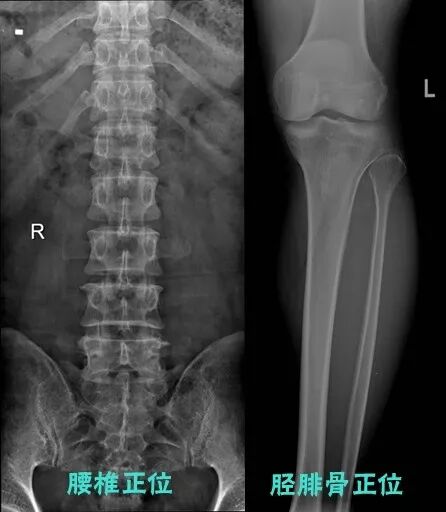

下列圖片能夠清晰對比出傳統(tǒng)與新技術(shù)的區(qū)別:

傳統(tǒng)技術(shù)影像